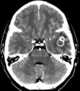

Radiation-induced telangiectasia